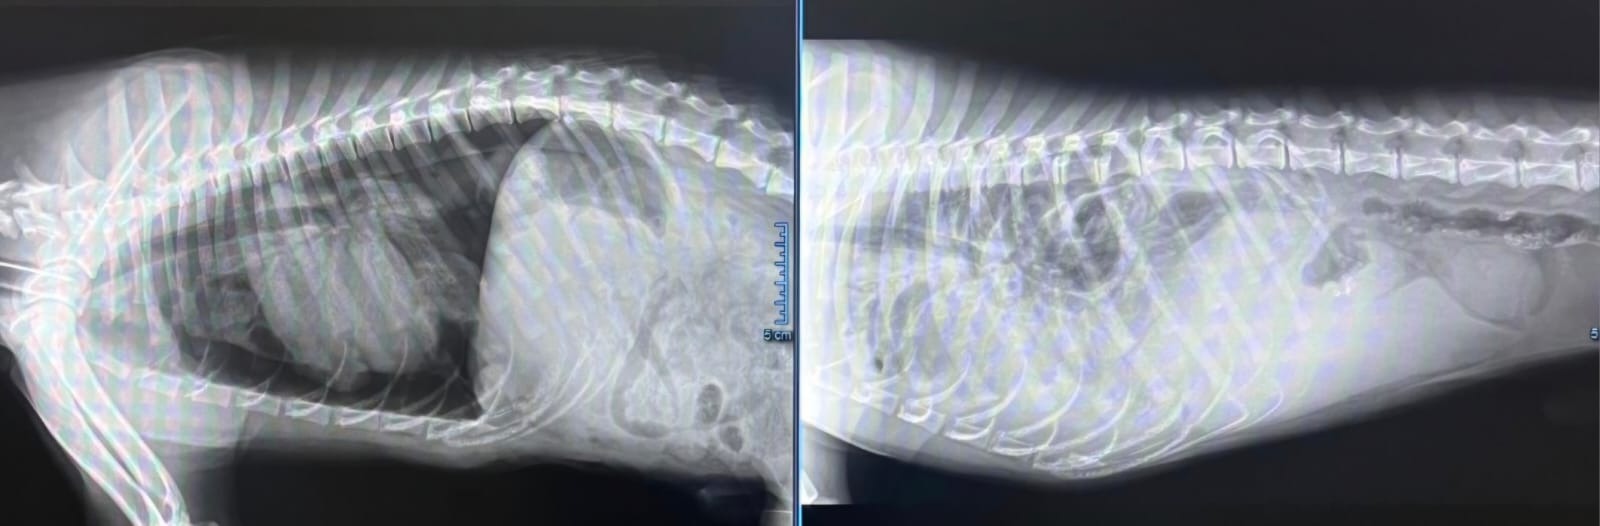

A gennaio, subito dopo Natale, vengo a sapere di un cucciolo di 5 mesi circa che vive accampato in una stazione di servizio vicino ad una strada pericolosa, esposto alle intemperie ed alla fame. Corro a salvarlo, appena in tempo perché il giorno seguente una bufera di vento e neve lo avrebbe ucciso. Grazie ad un ragazzo che lo segnalò , lo porto a casa della mia amica Tina che da subito gli ha donato amore ed attenzioni e decidiamo di chiamarlo Angelo, perché la sua presenza dolce e buona, la sua bellezza infinita, ricordano una creatura celestiale. Angelo è provato, dopo un periodo di tranquillità manifesta dei sintomi strani, ci rechiamo da un veterinario e ci dice che forse ha ingerito dei cibi inadatti a lui ... si provvede a perette e alimentazione ad hoc ma nulla. Ci rechiamo da un altro veterinario che ci dà una cura per tracheite ma il cane è a fasi alterne e ha alti e bassi. Da pochi giorni Angelo peggiora, non gioca più con, non vuole mangiare.. Decidiamo di recarci altrove in data odierna dove abbiamo trovato veri professionisti. La diagnosi è nefasta: grave ernia diaframmatica che ha provocato lo spostamento di tutti gli organi all'interno del torace. Dovuto ad un trauma, probabilmente Angelo veniva preso a calci da piccolino quando viveva in strada, prima che lo trovassimo noi. Ora rischia di morire! È grave, ma noi non molliamo perché lo abbiamo salvato dalla strada e non lo lasceremo andare via così! Decidiamo di dare il consenso per un intervento chirurgico complesso e difficile, che forse lo salverà. Ma non abbiamo fondi e la clinica ci fa un preventivo di 900 euro iniziali , per lintervento e a questi si allegheranno degenza e farmaci per un totale di oltre 1400€.Aiutateci a pagare la clinica, perché non abbiamo badato a spese per salvare questo angelo caduto dal cielo, deve tornare a casa, fra le braccia di Tina, che da subito si è offerta di tenerlo e amarlo . Non abbiamo le risorse economiche per curarlo ma abbiamo un cuore grande per non farlo morire dopo averlo salvato. Sono certa che un piccolo contributo di ognuno aiuterà a salvare questo Angelo sceso dal cielo e sarà una vittoria per tutti noi. Grazie a chiunque collabori. Il post sarà aggiornato man mano con miglioramenti se Dio vuole e le successive fasi del cane.

Angelo è stato operato. L'intervento in emergenza durato due ore, è riuscito. Gli organi sono stati rimessi a posto ed ora è vigile e reattivo . Dobbiamo aspettare che trascorrano 48 ore per dire se è davvero fuori pericolo ma i medici veterinari sono fiduciosi! Ora è nella terapia intensiva costantemente monitorato.